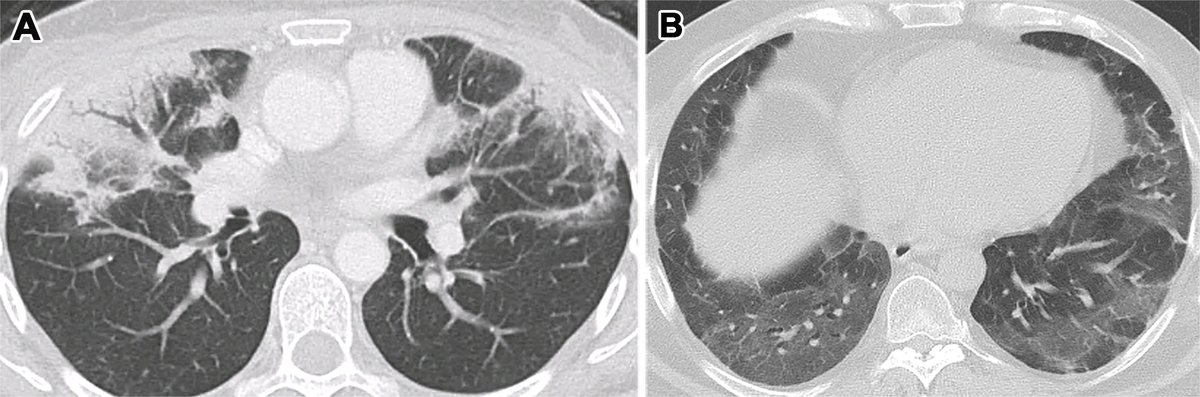

Diffuse alveolar damage (DAD) and organizing pneumonia (OD) are the major manifestations of lung injury. Learn how to best participate in a multidisciplinary approach to patients with lung injury. bit.ly/3NVUtsj

#12 The Many Faces of Organizing Pneumonia (OP) 🎭 1⃣ OP is a term used to describe a nonspecific response to lung injury (infection, drugs, RT, autoimmunity, cryptogenic...) 🫁 Radiological features of OP are wide: consolidation, GG, nodules & other more specific features ➡️🧵

Radiological features of OP are wide: consolidation, GG, nodules & other more specific features ➡️🧵